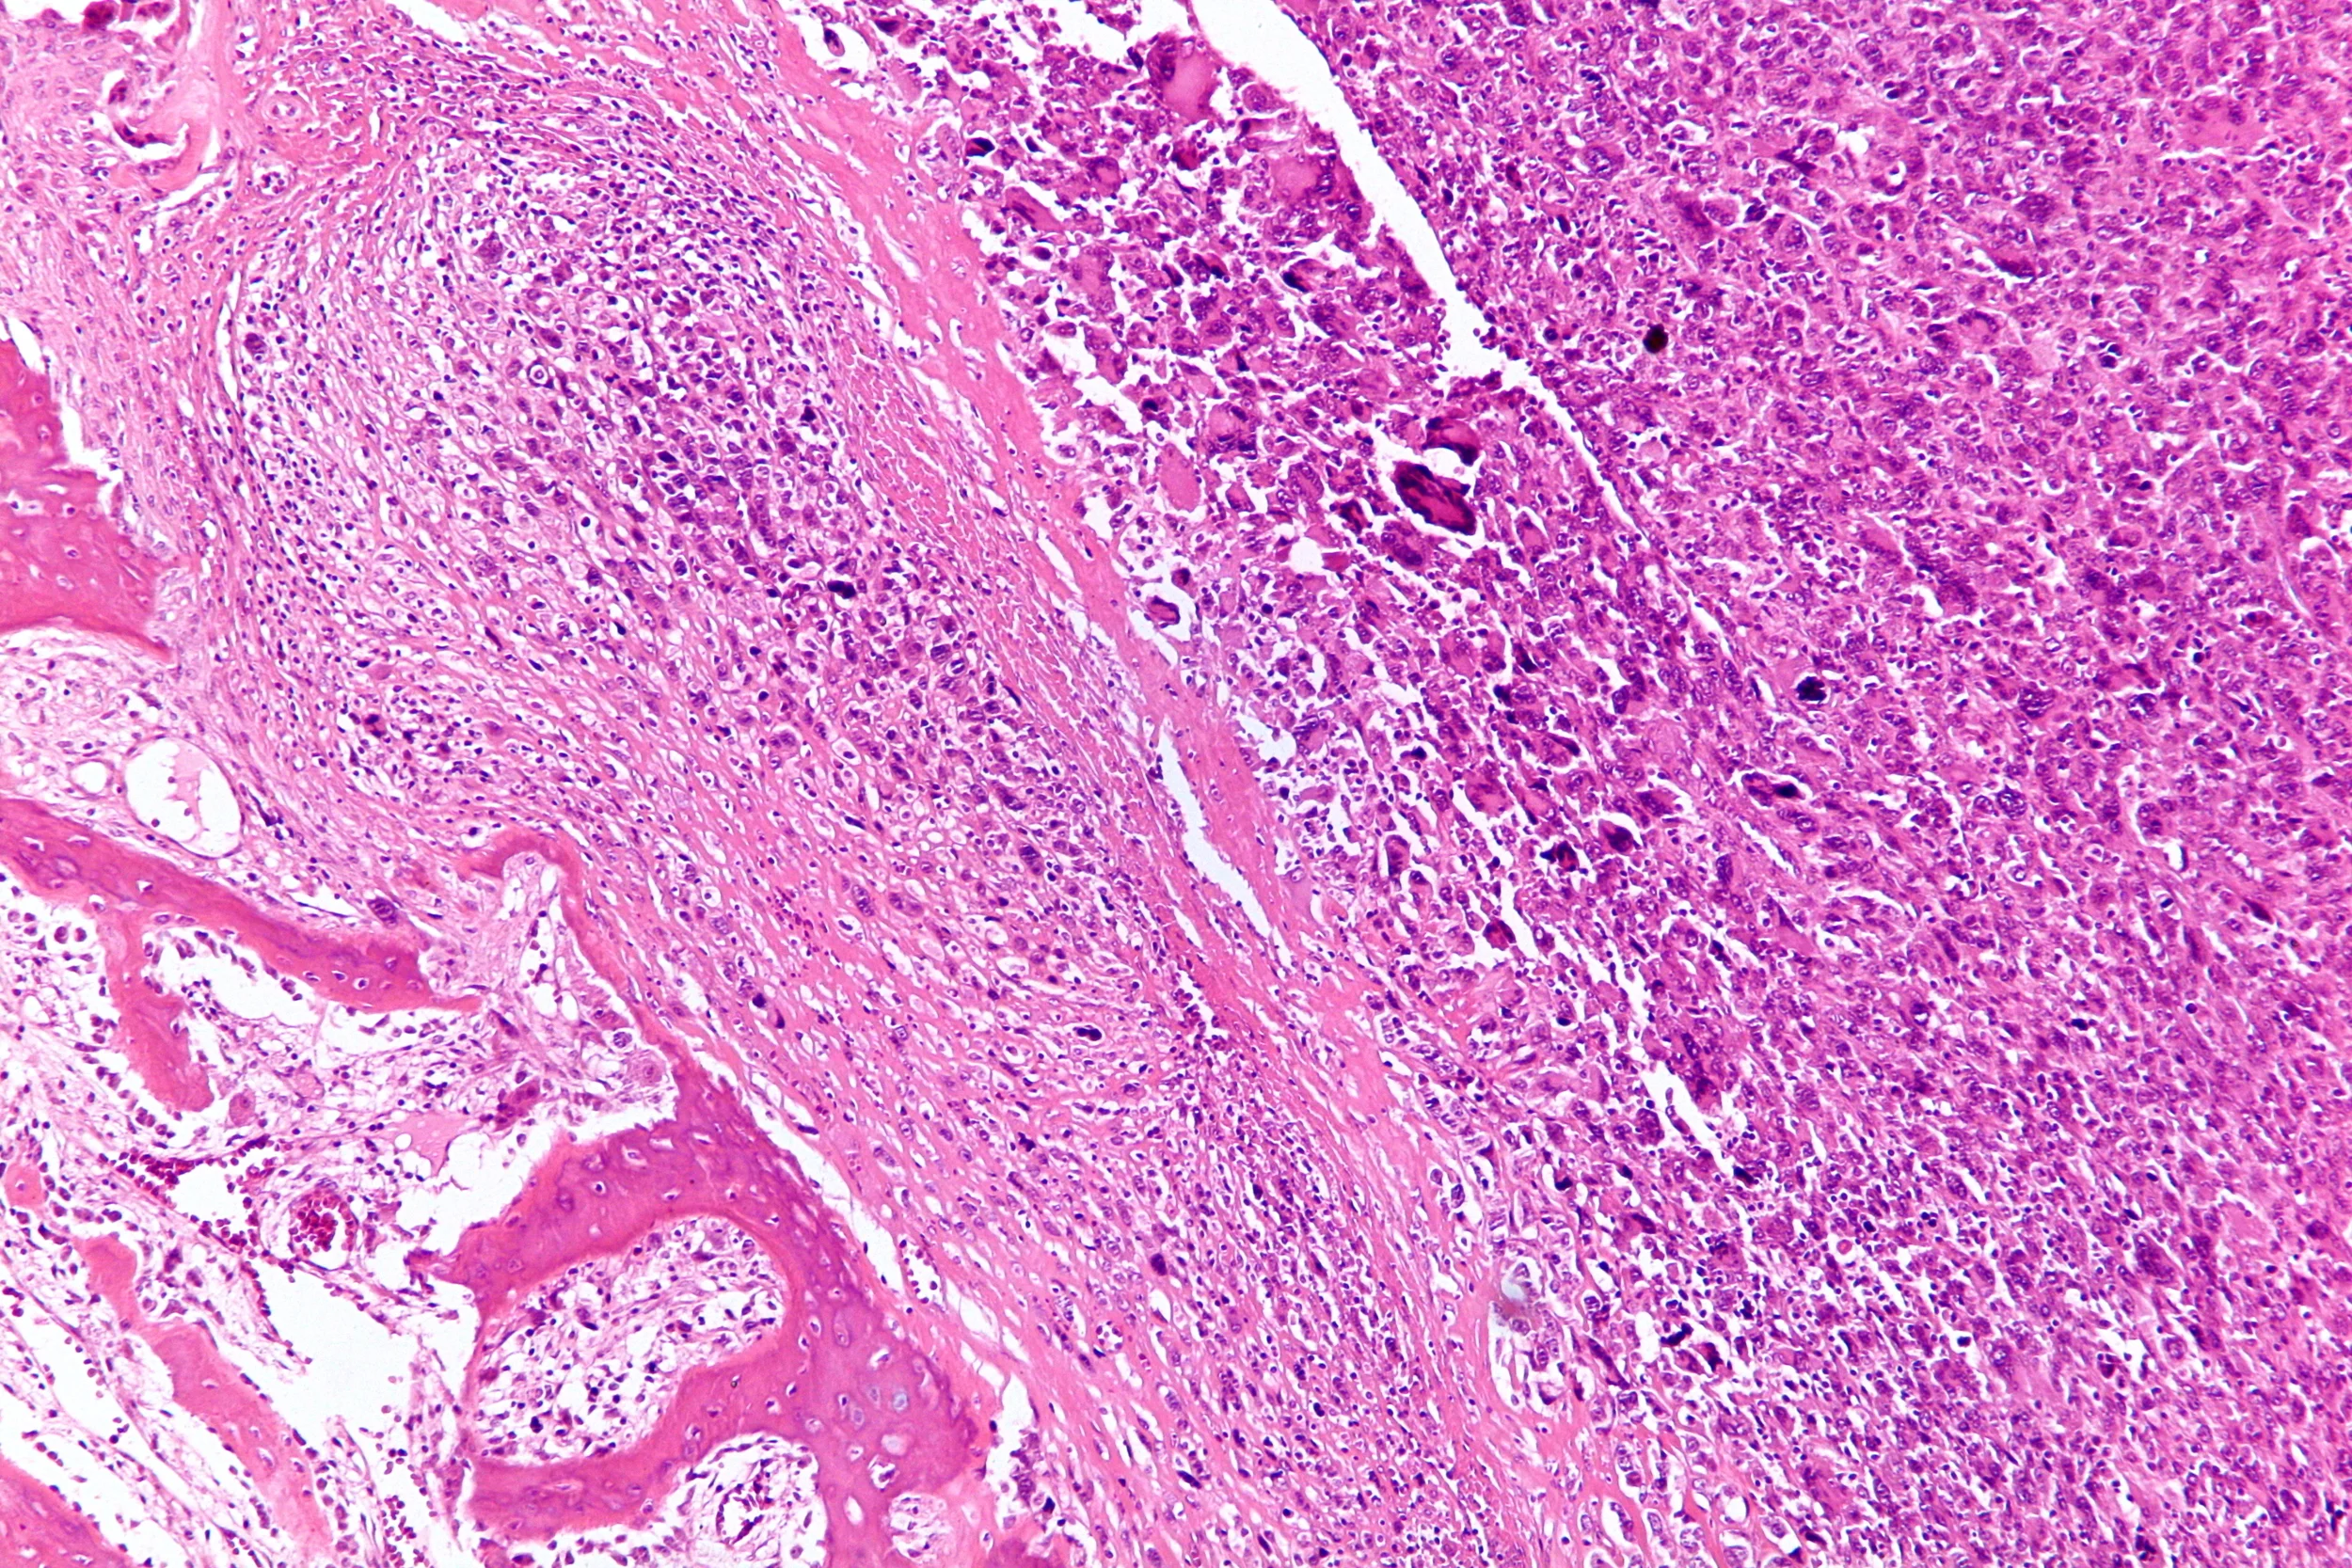

Osteosarcoma under the microscope. Photo credit: Nephron via Creative Commons license.